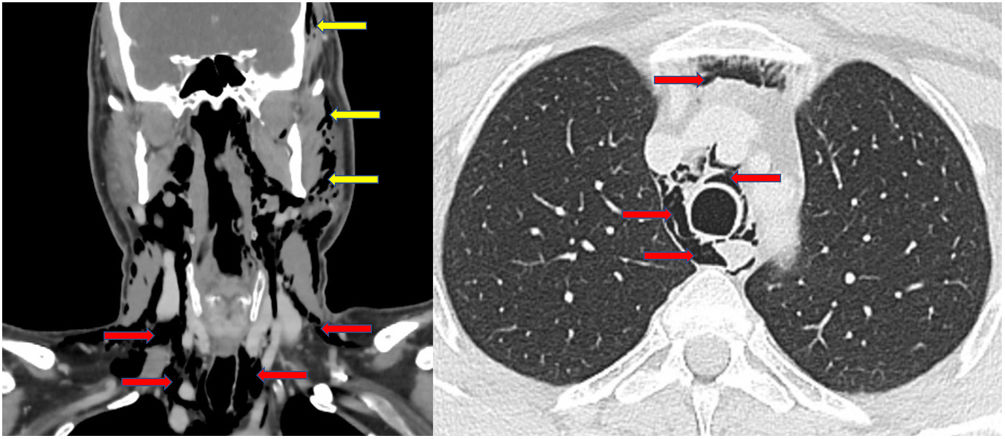

Medicina Clínica A rare cause of pneumomediastinum

A rare cause of pneumomediastinum

Una causa rara de neumomediastino